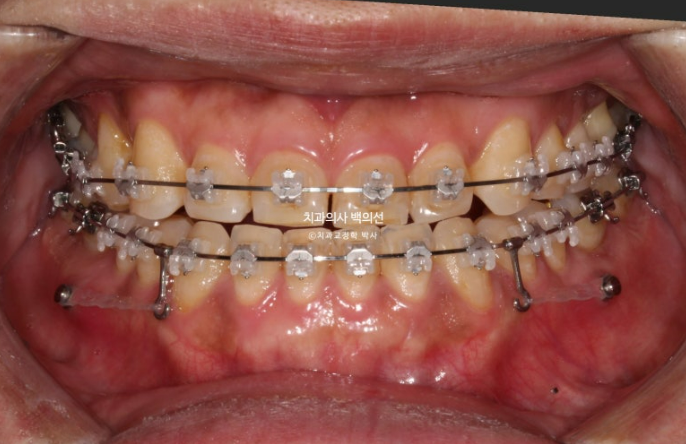

23년 7월 앞니 거꾸로 물림을 교정으로 해결하고자 내원하신 30대 남성분

아랫니에 가려서 잘 보이지는 않지만

23.07

앞니 마모가 상당히 심합니다.

거꾸로 물리는 상태로 오래 지내오다보니, 아랫니와 닿는 부분들이 마모가 된 것입니다.

마모도를 보면 교합력도 상당히 센 편임을 알 수 있습니다.

비발치로 아래 전체 치열을 사랑니 공간으로 밀어서 앞니 반대교합을 해소하기로 했습니다.

클리피씨 교정을 선택하셨고 먼저 아래 장치 부착 후 치료를 시작했습니다.

아래 장치 부착 4개월 후 위 장치 부착을 했습니다.